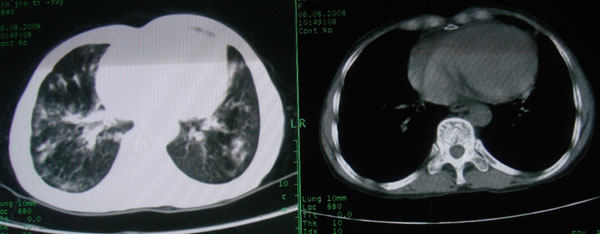

慢性支气管炎伴支气管扩张\\感染

慢性支气管病变并肺部感染。

支持慢性支气管病变并肺部感染。

肺间质性改变 支气管扩张合并感染

慢性支气管炎伴全小型肺气肿、支气管扩张、感染、间质纤维化。